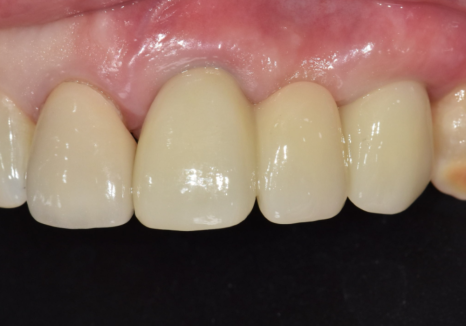

오래된 앞니 크라운 냄새, '이것' 때문일 수 있습니다.

앞니 임플란트는

단순히 튼튼하게 심는 것을 넘어

'옆 치아와 얼마나 자연스럽게 어울리는가'가

생명입니다.

특히 이 환자분처럼 주변 치아도 크라운인 경우,

색상이나 각도가 조금만 어긋나도

매우 어색한 인상을 줄 수 있는데요~

저희가 최적의 결과를 낼 수 있는 비결은

치과 내부에 전용 기공소가 있기 때문입니다.

어떠세요? 주변 치아와 조화를 이루며

아주 자연스럽게 마무리된 모습이죠?

단순히 심는 것에 그치지 않고

뼈 상태, 잇몸 회복,그리고 정교한 교합까지

세밀하게 고려하여 자연스러운 보철이

완성되었습니다.^^